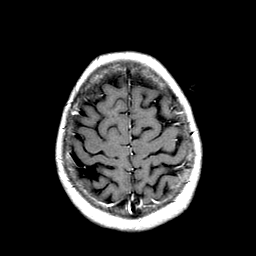

Metastatic Adenocarcinoma of the Colon: T1-weighted MR -- Slice #20

[Home][Help][Clinical] Slice 20